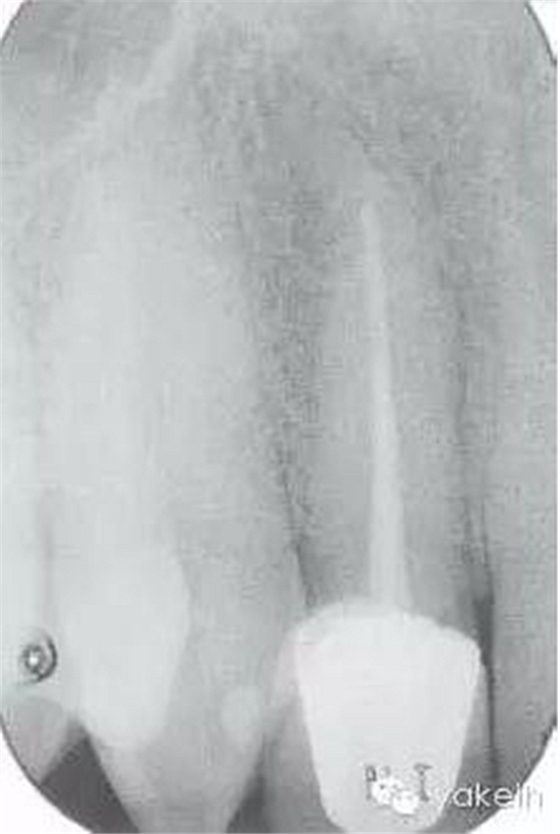

12根尖X線片顯示什么(圖6.3.1)?

● 根尖PDL增寬。

● 根管欠充。

圖6.3.1根尖X線片顯示,12根管治療后根尖周透射影。